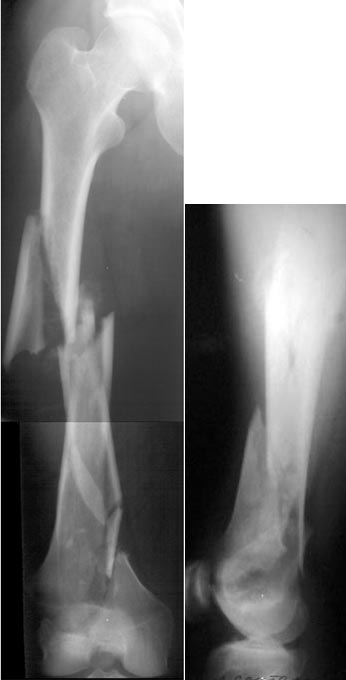

of course the only radiograms both the view of the femur (AP and LL) are not enough in order to assess the condilar ones.

Are you sure you want to operate this patient?

He survived 1 month on traction, the most difficult part of it!

The best healing is anticipated if the fracture site is not opened (virtually the whole thigh in your tough case!).

ExFix could be good biologically, what kind of frame would you use?

IM nailing, may be retrograde (for sure not

antegrade), either way it would be very-very

difficult.

I am sure that you assessed adequately the condylar fractures, they may need fixation (eg. percutaneous screws).

I tried to think of LISS, but it would be difficult to perform after a month (no fracture hematoma but there is fibrosus callus formation). And even the longest LISS would be short here, not to mention the very small distal piece.

ORIF would not be good for the fracture healing and a disaster for the patient.

A CT and knee xrays would help identify lateral condyle comminution and/or a "hoffa fragment" of the posterior condyle. I am concerned that the lateral cortex is not sufficient to give purchase for a retrograde IMN. blocking screws could improve this as a possibility. A long blade or LISS if avaible would be my secondary choices. Good luck. Any chance you can get these cases transferred earlier when it

Lateral condyle looks too small for the blade, and the plate too short.